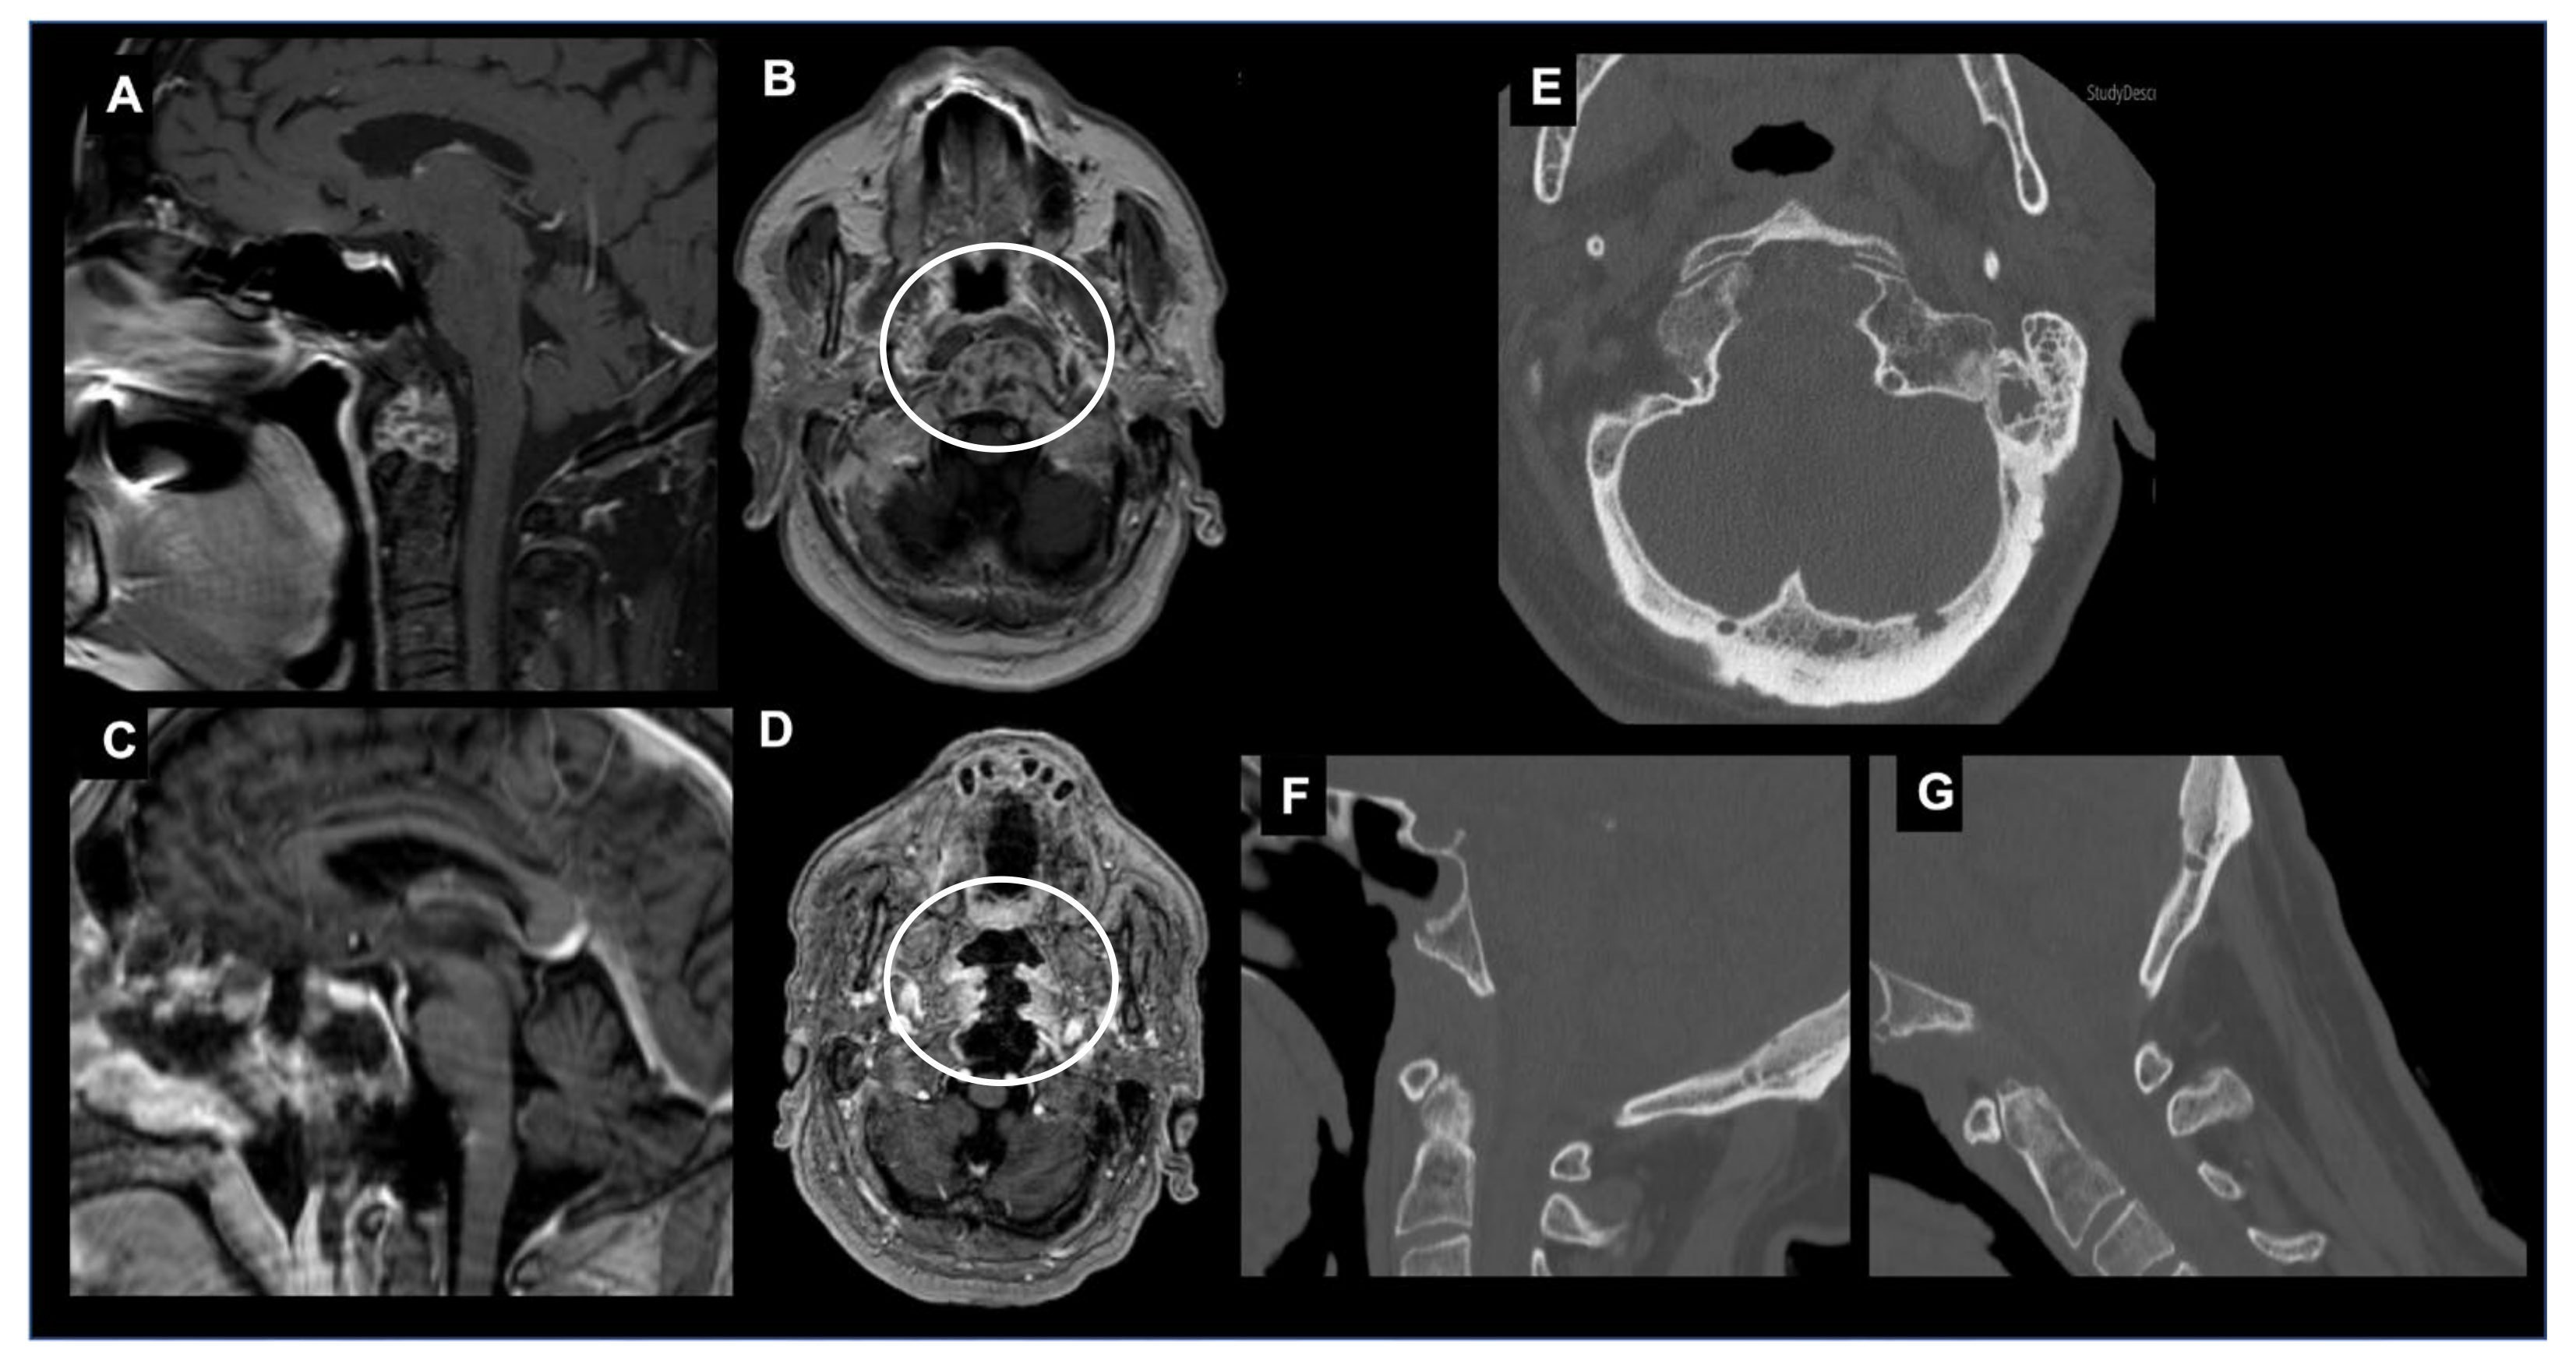

The posterior and posterolateral approaches represent two further operative techniques for the treatment of CVJ primary and metastatic neoplastic diseases available in the neurosurgical armamentarium (Figure 6).

Figure 6.

Combined endoscopic endonasal approach and far-lateral transcondylar and petro-occipital trans-sigmoid approach to recurrent CVJ chordoma and subsequent occipitocervical fixation. Axial T2-weighted MR image (A) and angio CT scan (B) showing a recurrent predominantly right craniovertebral junction chordoma. The chordoma infiltrates the rhinopharynx, C0-C1-C2 joint complex and the entire right occipital condyle. A combined endoscopic endonasal approach associated with far-lateral transcondylar and petro-occipital trans-sigmoid approach has been performed. (C) Axial postoperative T1-weighted after contrast injection image and (D) noncontrast CT scan disclosed a gross total resection with the destruction of the right clival–atlo–axial joint. An occipital-cervical fixation was therefore postoperatively planned and performed (E,F).